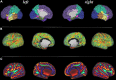

The Developing Human Connectome Project has created a large open science resource which provides researchers with data for investigating typical and atypical brain development across the perinatal period. It has collected 1228 multimodal magnetic resonance imaging (MRI) brain datasets from 1173 fetal and/or neonatal participants, together with collateral demographic, clinical, family, neurocognitive and genomic data from 1173 participants, together with collateral demographic, clinical, family, neurocognitive and genomic data. All subjects were studied in utero and/or soon after birth on a single MRI scanner using specially developed scanning sequences which included novel motion-tolerant imaging methods. Imaging data are complemented by rich demographic, clinical, neurodevelopmental, and genomic information. The project is now releasing a large set of neonatal data; fetal data will be described and released separately. This release includes scans from 783 infants of whom: 583 were healthy infants born at term; as well as preterm infants; and infants at high risk of atypical neurocognitive development. Many infants were imaged more than once to provide longitudinal data, and the total number of datasets being released is 887. We now describe the dHCP image acquisition and processing protocols, summarize the available imaging and collateral data, and provide information on how the data can be accessed.